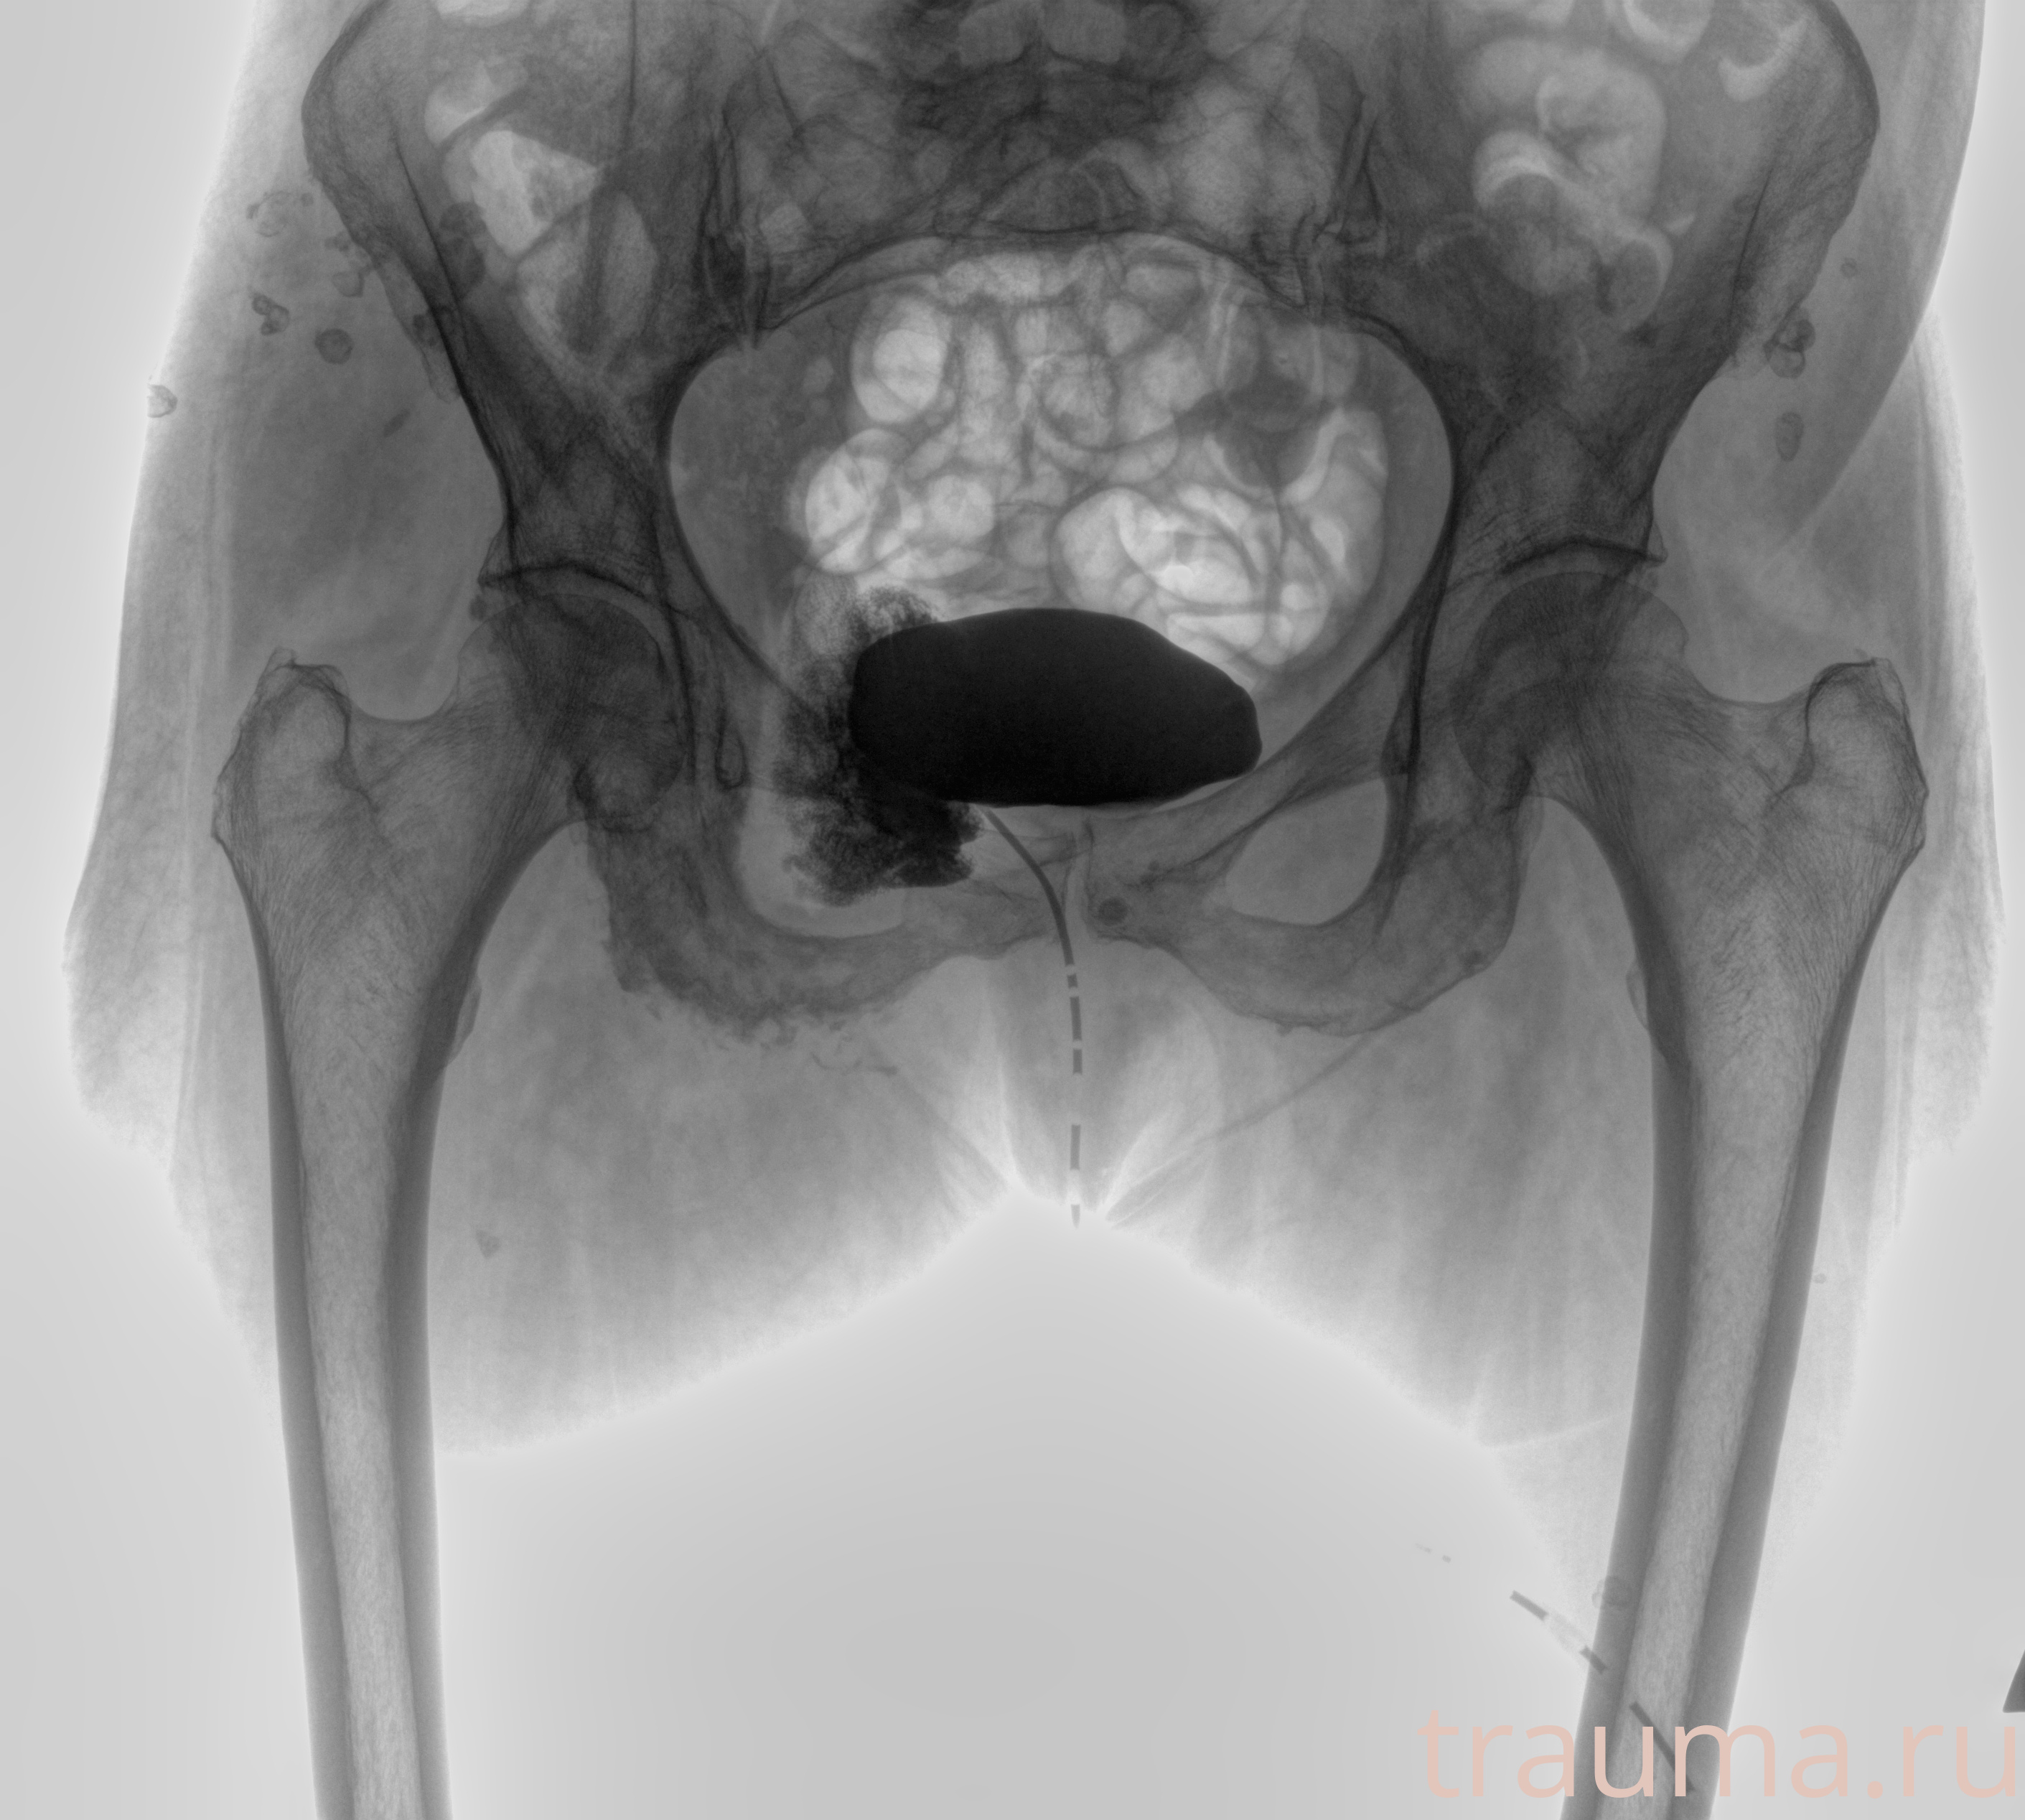

Рентгенограммы

Рентген на дому: по вашему адресу приезжает врач-рентгенолог, травматолог-ортопед с мобильным рентгеновским аппаратом, проводит диагностику травмы или заболевания, делает необходимые рентгенограммы, дает рекомендации по дальнейшему лечению. Получить качественные снимки в домашних условиях возможно благодаря уникальной методике, разработанной МосРентген Центром для института  Склифосовского